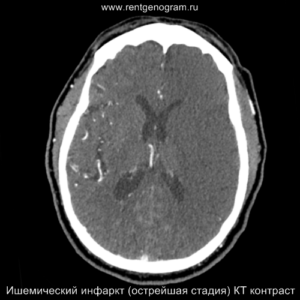

Острая фаза (6 — 24 часа)

В течение острого этапа на МРТ и КТ выявляются все морфологические признаки ишемического инсульта. Область острого ишемического инфаркта визуализируется как зона ↑Т2, ↑Flair, ↑DWI и ↓Т1 ↓ADC. Можно обнаружить тромб в артерии. На КТ в остром этапе также чётко дифференцируется поражённая область, представляющая собой участок с потерей дифференциации мозговых структур и снижением их плотности. Контрастирование в остром периоде не показывает патологических участков с накоплением контраста.

Подострая фаза (24 часа — 6 недель)

На подостром этапе происходит разрушение гематоэнцефалического барьера, что приводит к вазогенному отеку, увеличивая объем ишемического инфаркта, возникновение масс-эффекта и возможного вклинения в случае обширного поражения (например, вклинение поясной извилины под фалькс или миндалин мозжечка в большое затылочное отверстие).

Разрушение гематоэнцефалического барьера (ГЭБ) приводит к накоплению контрастного вещества в области ишемического инсульта, используя технику контрастирования по «гиральному типу».